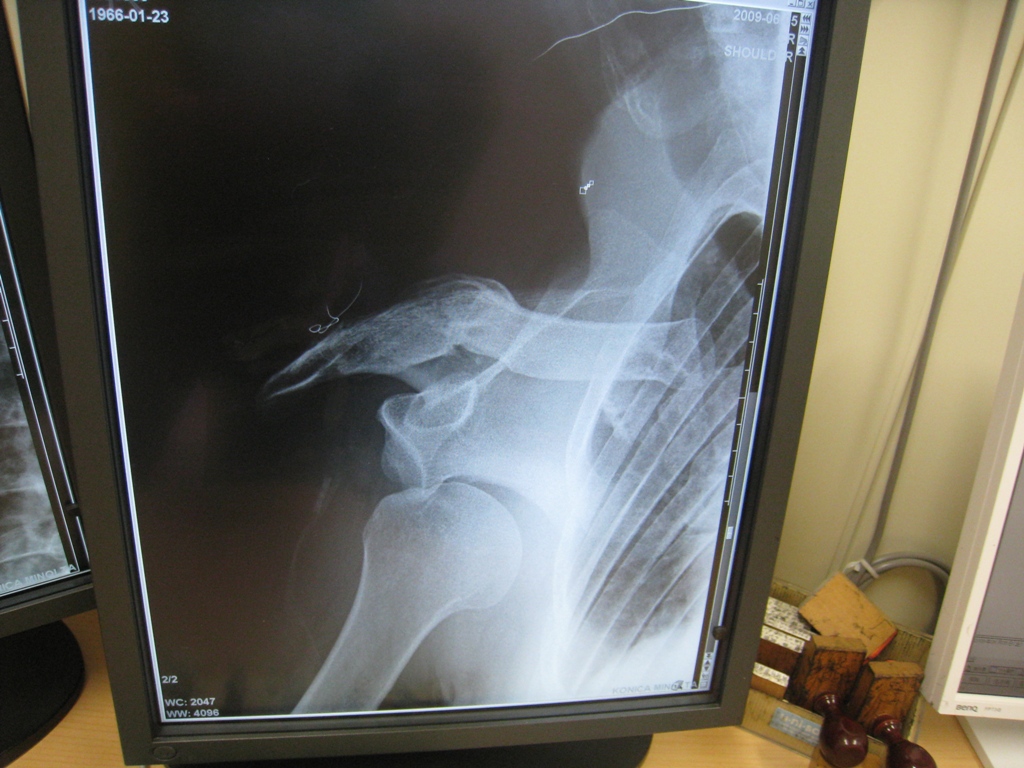

(写真左が脱臼しているレントゲン画像で、写真右が元に戻した後の画像)

左の写真は肩が下がり、残った部分はまるで、プロテクターのようになっていた。

骨を折る場所にもよるが、鎖骨折るよりは、はるか~に痛かった!